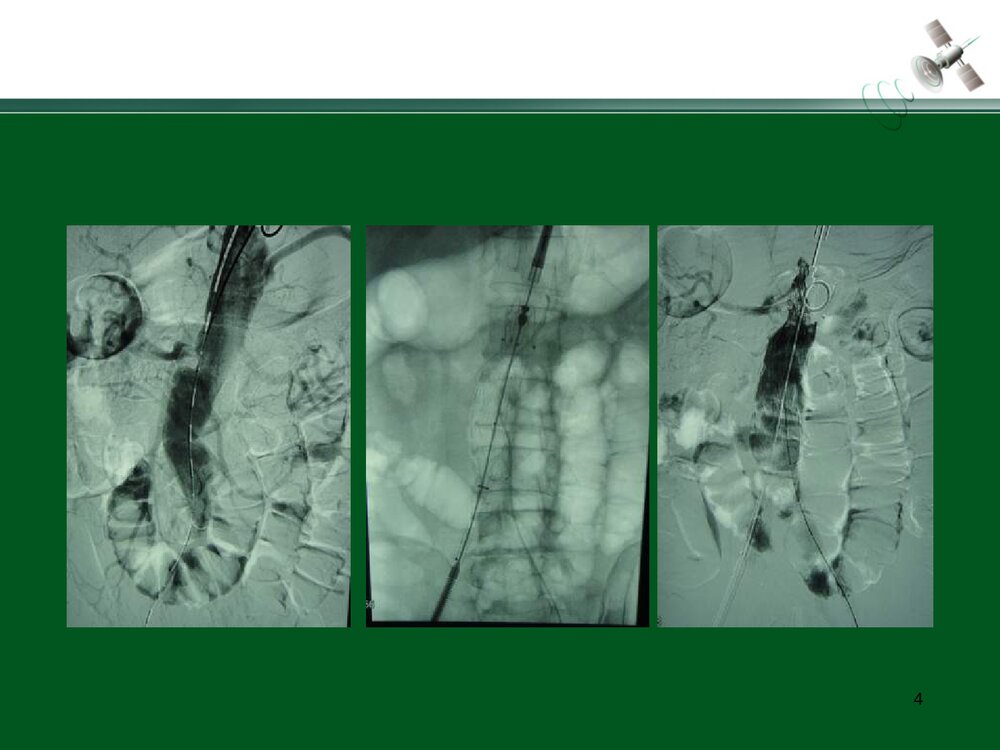

复杂腹主动脉瘤的腔内治疗常光其王深明教育部国家重点学科卫计委国家临床重点专科中山大学附属第一医院血管外科中山大学血管外科研究中心1复杂瘤颈AAA的腔内治疗复杂瘤颈指下列情况1.瘤颈长度小于15mm;2.瘤颈角度大于60度;3.瘤颈直径过大或过小(小于18mm或大于32mm)例1:短瘤颈AAA的EVAR3456例2:短瘤颈伴入路血管狭窄AAA的EVAR7891011例3:瘤颈狭窄且成角大于60度AAA的EVAR12131415161718192021例4:瘤颈成角大于60度AAA的EVAR2223242526例5:瘤颈成角伴腹主动脉分叉狭窄AAA的EVAR272829303132复杂入路AAA的腔内治疗复杂入路是指下列情况:(1)髂动脉弯曲成角超过90°;(2)双侧髂股动脉广泛钙化伴严重狭窄,直径小于7mm;(3)双侧髂股动脉闭塞例6:入路血管严重狭窄AAA的EVAR34353637383940例7:入路血管严重...